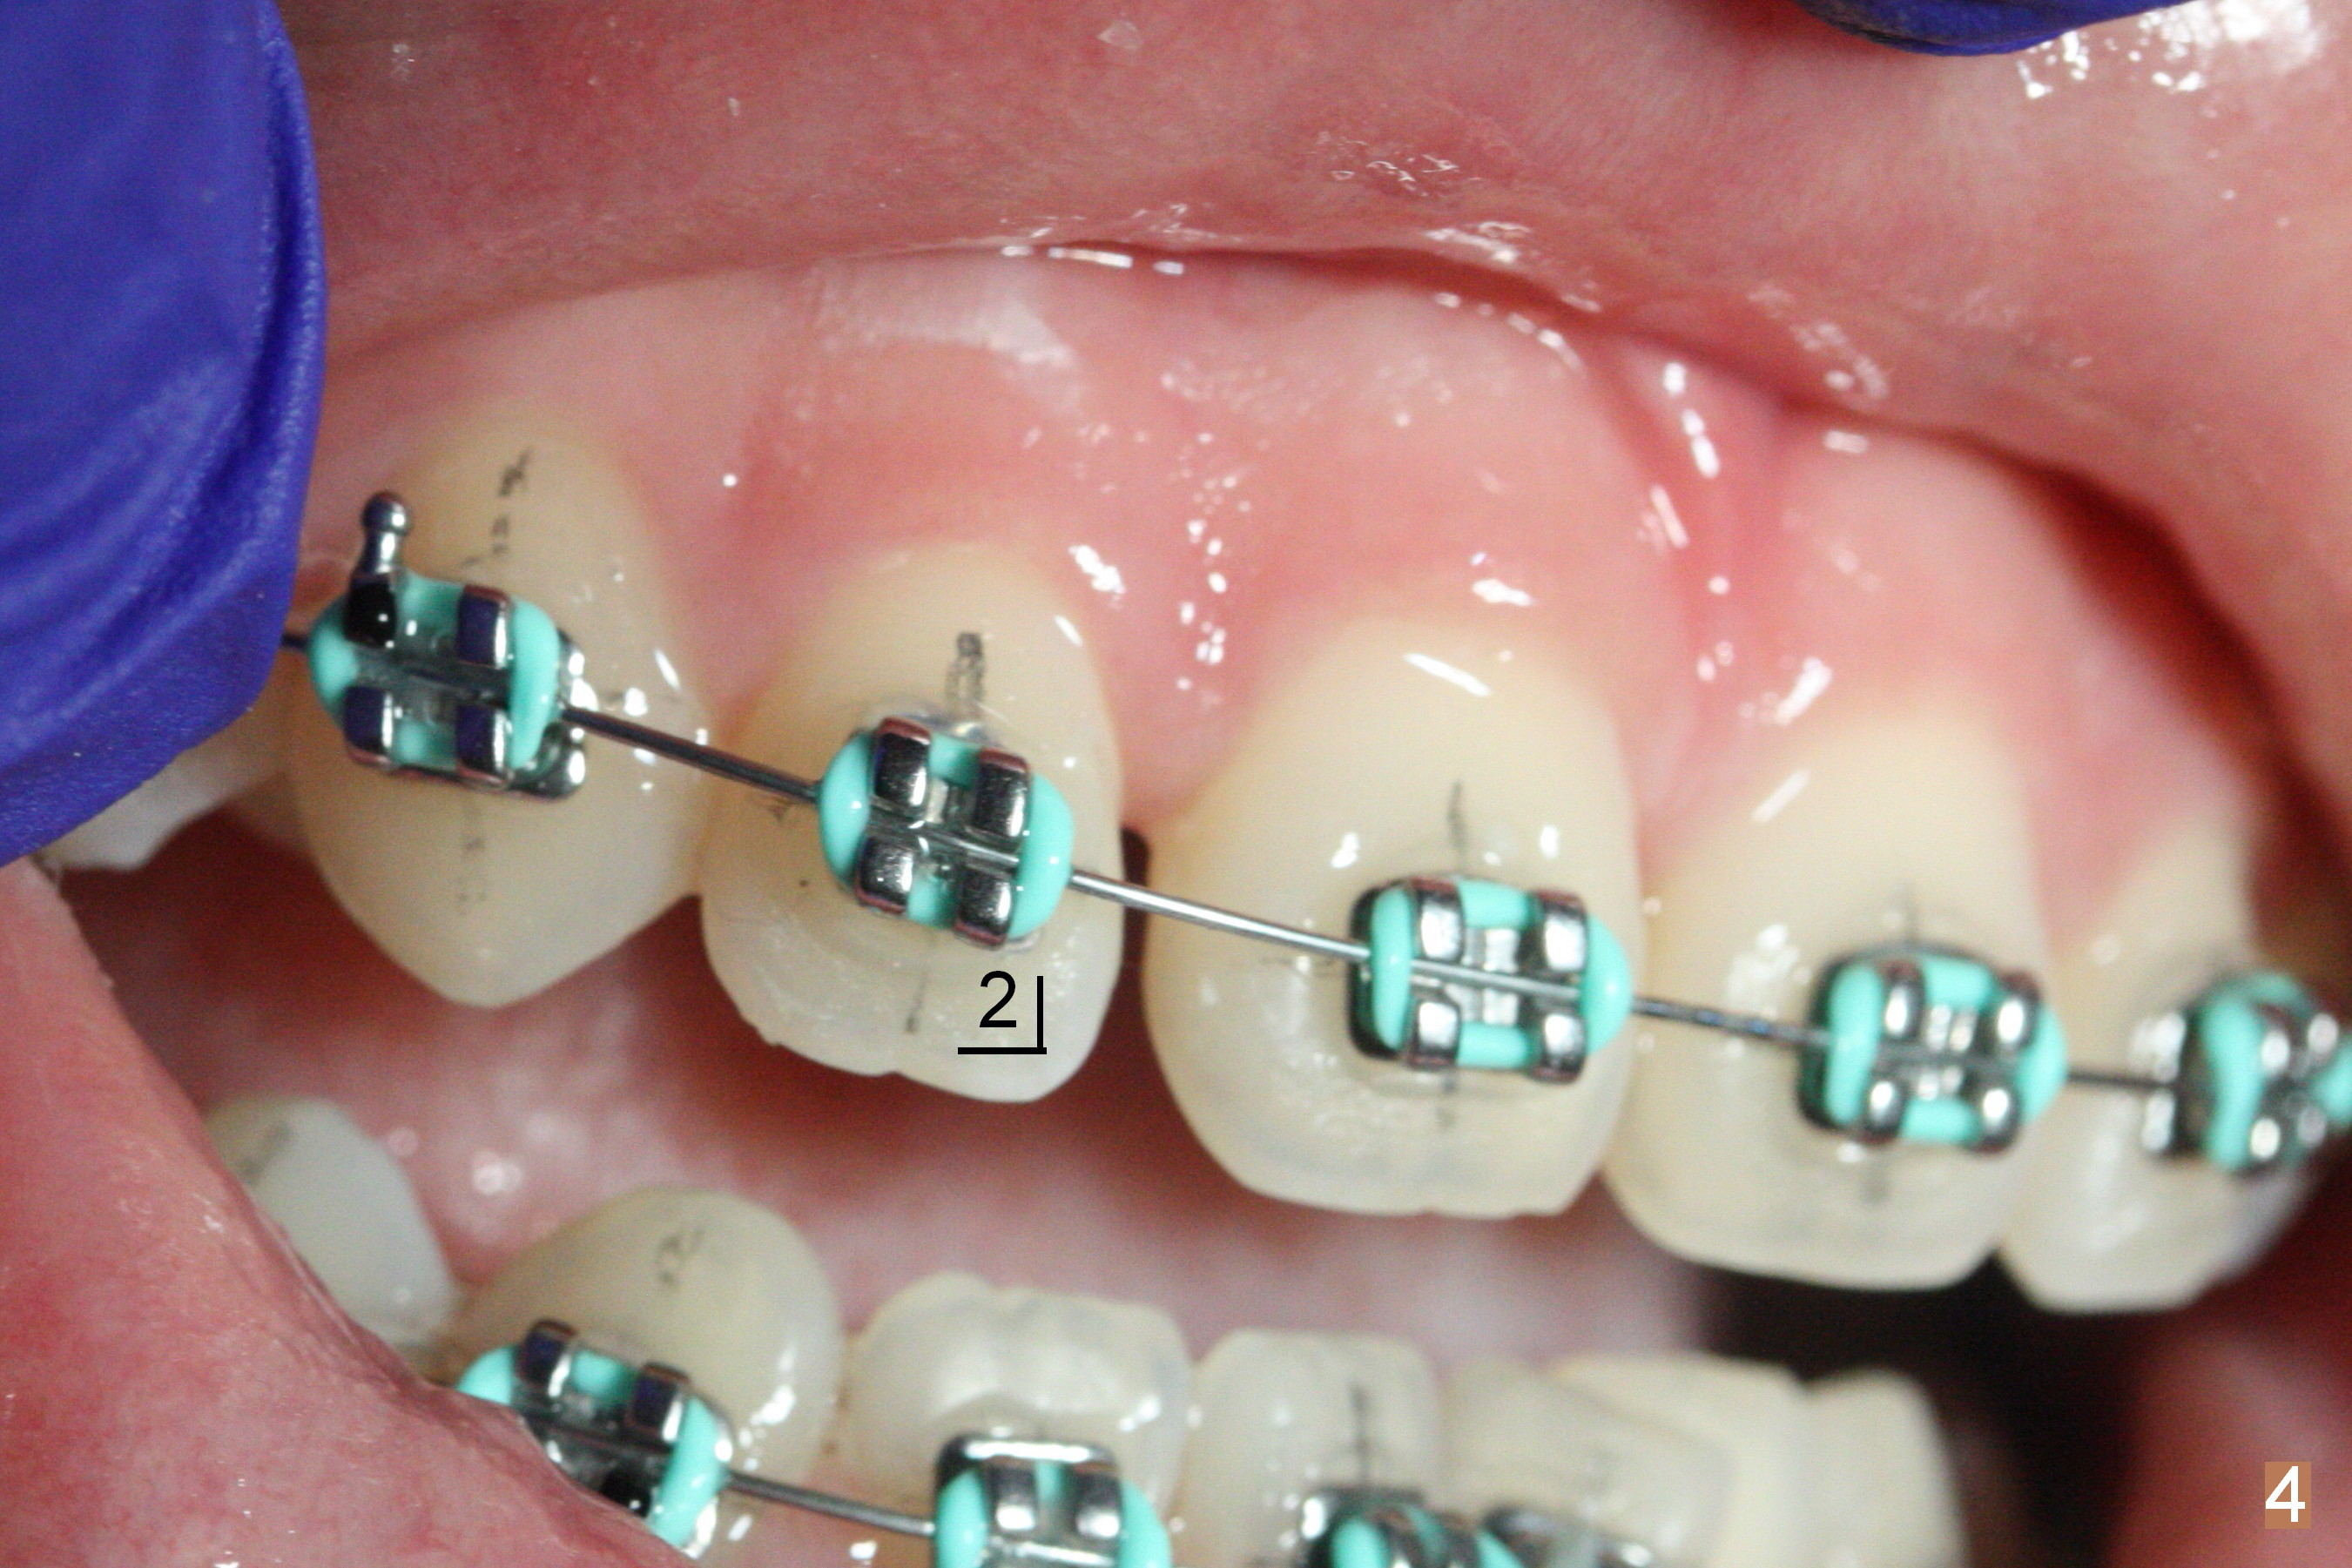

Before debanding, her young brother reports relapse due to loss of the lower suck down retainer and her preop model is reviewed (Fig.9). What are/is the appropriate retainer(s) for her?